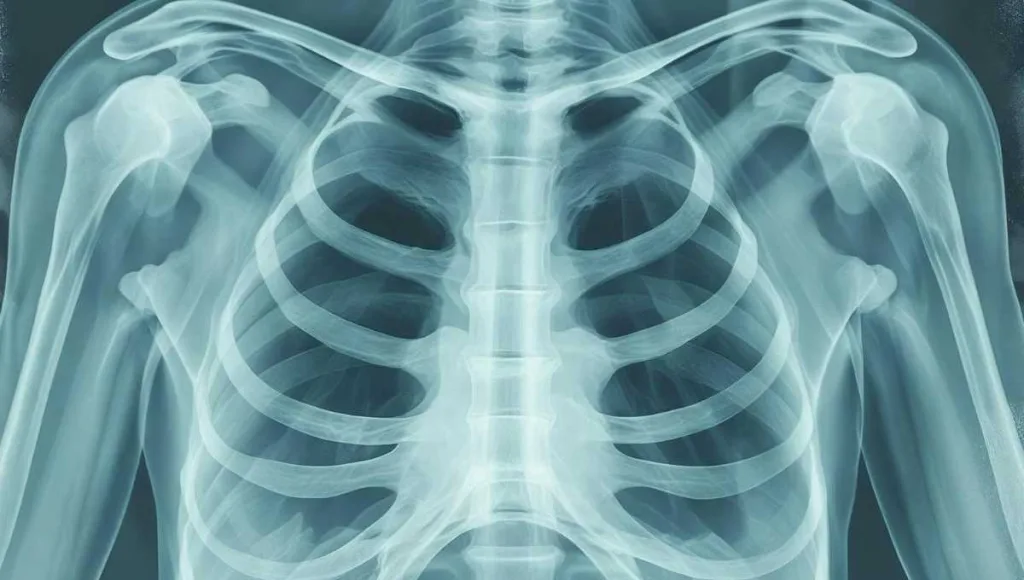

ٹی بی کی تشخیص کے لیے بلغم کا ٹیسٹ کروایا جاتا ہے۔ ٹی بی کی ادویات بھی سرکاری ہسپتاال سے مفت حاصل کی جا سکتی ہیں۔ فعال ایکٹیو ٹی بی کی بیماری مائیو بیکٹریریم ٹیوبرکلوسس جیسے ایک بیکٹیریا کے انفیکش کی وجہ سے ہوتی ہے۔ ٹی بی بالعموم انسان کے پھیپھڑوں کو متاثر کرتی ہے۔

لیکن کبھی کبھار یہ جسم کے دوسرے حصوں کو بھی متاثر کر سکتی ہے۔ جیسا کہ لمف غدود، گردے اور ہڈیاں وغیرہ متاثر کرتی ہے۔ ٹی بی کی بالعموم کوئی علامات یا اثرات نہیں ہوتے دوسررا یہ کہ زیادہ تر ٹی بی کے جرثیم زیادہ افعال نہیں ہوتے۔ اس طرح کی ٹی بی کو خوابیدہ یا مخفی ٹی بی انفیکشن کہتے ہیں۔ مخفی انفیکشن کے حامل انسان سے دوسروں کو انفیکشن نہیں ہو سکتا اور وہ گھر کے افراد یا دوسرے قریبی واسطہ رکھنےوالوں کو جرثیم منتقل نہیں ہو سکتے۔